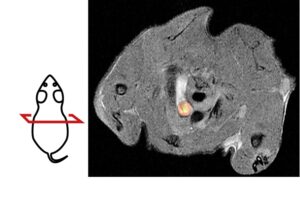

Mehr erfahren zu: "Roadmap zeigt den Einsatz Künstlicher Intelligenz in der radiologischen Herzbildgebung" Roadmap zeigt den Einsatz Künstlicher Intelligenz in der radiologischen Herzbildgebung Wie kann Künstliche Intelligenz (KI) die Diagnose von Herzerkrankungen und die Behandlung Betroffener verbessern? Antworten auf diese Frage gibt die in der Fachzeitschrift „Nature Reviews Cardiology“ veröffentlichte „Roadmap on the […]